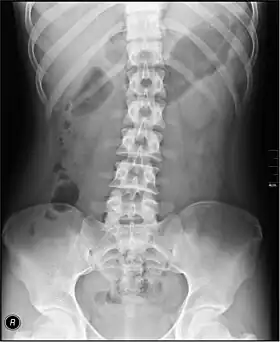

- Lumbar Spine - AP and Lateral +/- L5/S1 view in the UK, with obliques and Flexion and Extension requests being rare.[15] In the US, basic projections include an AP, two Obliques, a Lateral, and a Lateral L5-S1 spot to better visualize the L5-S1 interspace. Special projections are AP Right and Left bending, and Laterals with Flexion and Extension.